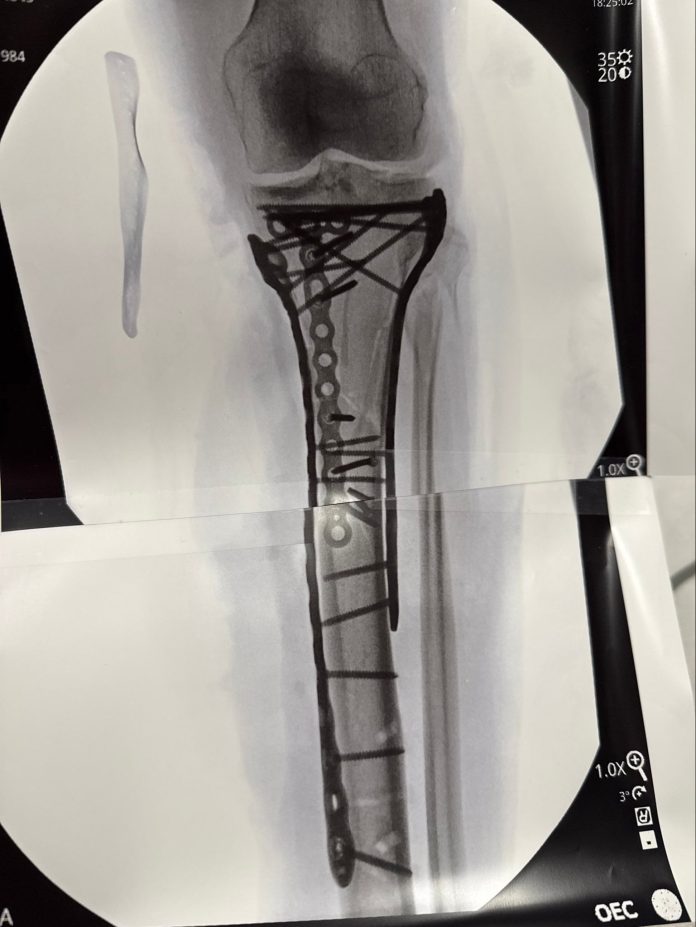

La radiografía que compartió Lindsey Vonn en sus redes sociales

La recuperación de Lindsey Vonn tras el impacto sufrido en los Juegos Olímpicos de Invierno de Milano-Cortina reveló imágenes que parecen irreales: una radiografía de su pierna izquierda con varios tornillos metálicos y placas que ahora forman parte de su anatomía. La propia Vonn se refirió a su condición con ironía: “Soy biónica de verdad ahora”, expresó y subrayó el impacto físico y mental de esta etapa.

Ya en su perfil de Instagram, profundizó en sus sensaciones y lo acompañó de un video de ella en la camilla y una imagen de la radiografía en cuestión: “Como pueden ver han sido necesarias muchas placas y tornillos para recomponerlo todo. Debido a la gravedad del traumatismo, he tenido algunas dificultades después de la operación y aún no me han dado el alta del hospital… pero ya casi estoy lista. Pasito a pasito. Pronto explicaré la lesión y lo que significa todo esto”.

El doctor Bertrand Sonnery-Cottet, referente en ortopedia y cirugía de rodilla, advirtió en una entrevista con RMC Sports sobre el riesgo real que afrontan pacientes con lesiones tan graves: “Algunas lesiones como la suya pueden acabar en amputación”, aunque aclaró que el caso de Vonn no llegó a ese punto. El procedimiento más reciente, que duró más de seis horas, implicó la utilización de numerosas placas y tornillos para estabilizar la fractura. La atleta agradeció al equipo médico y relató que el dolor fue intenso, lo que dificulta su recuperación inmediata.